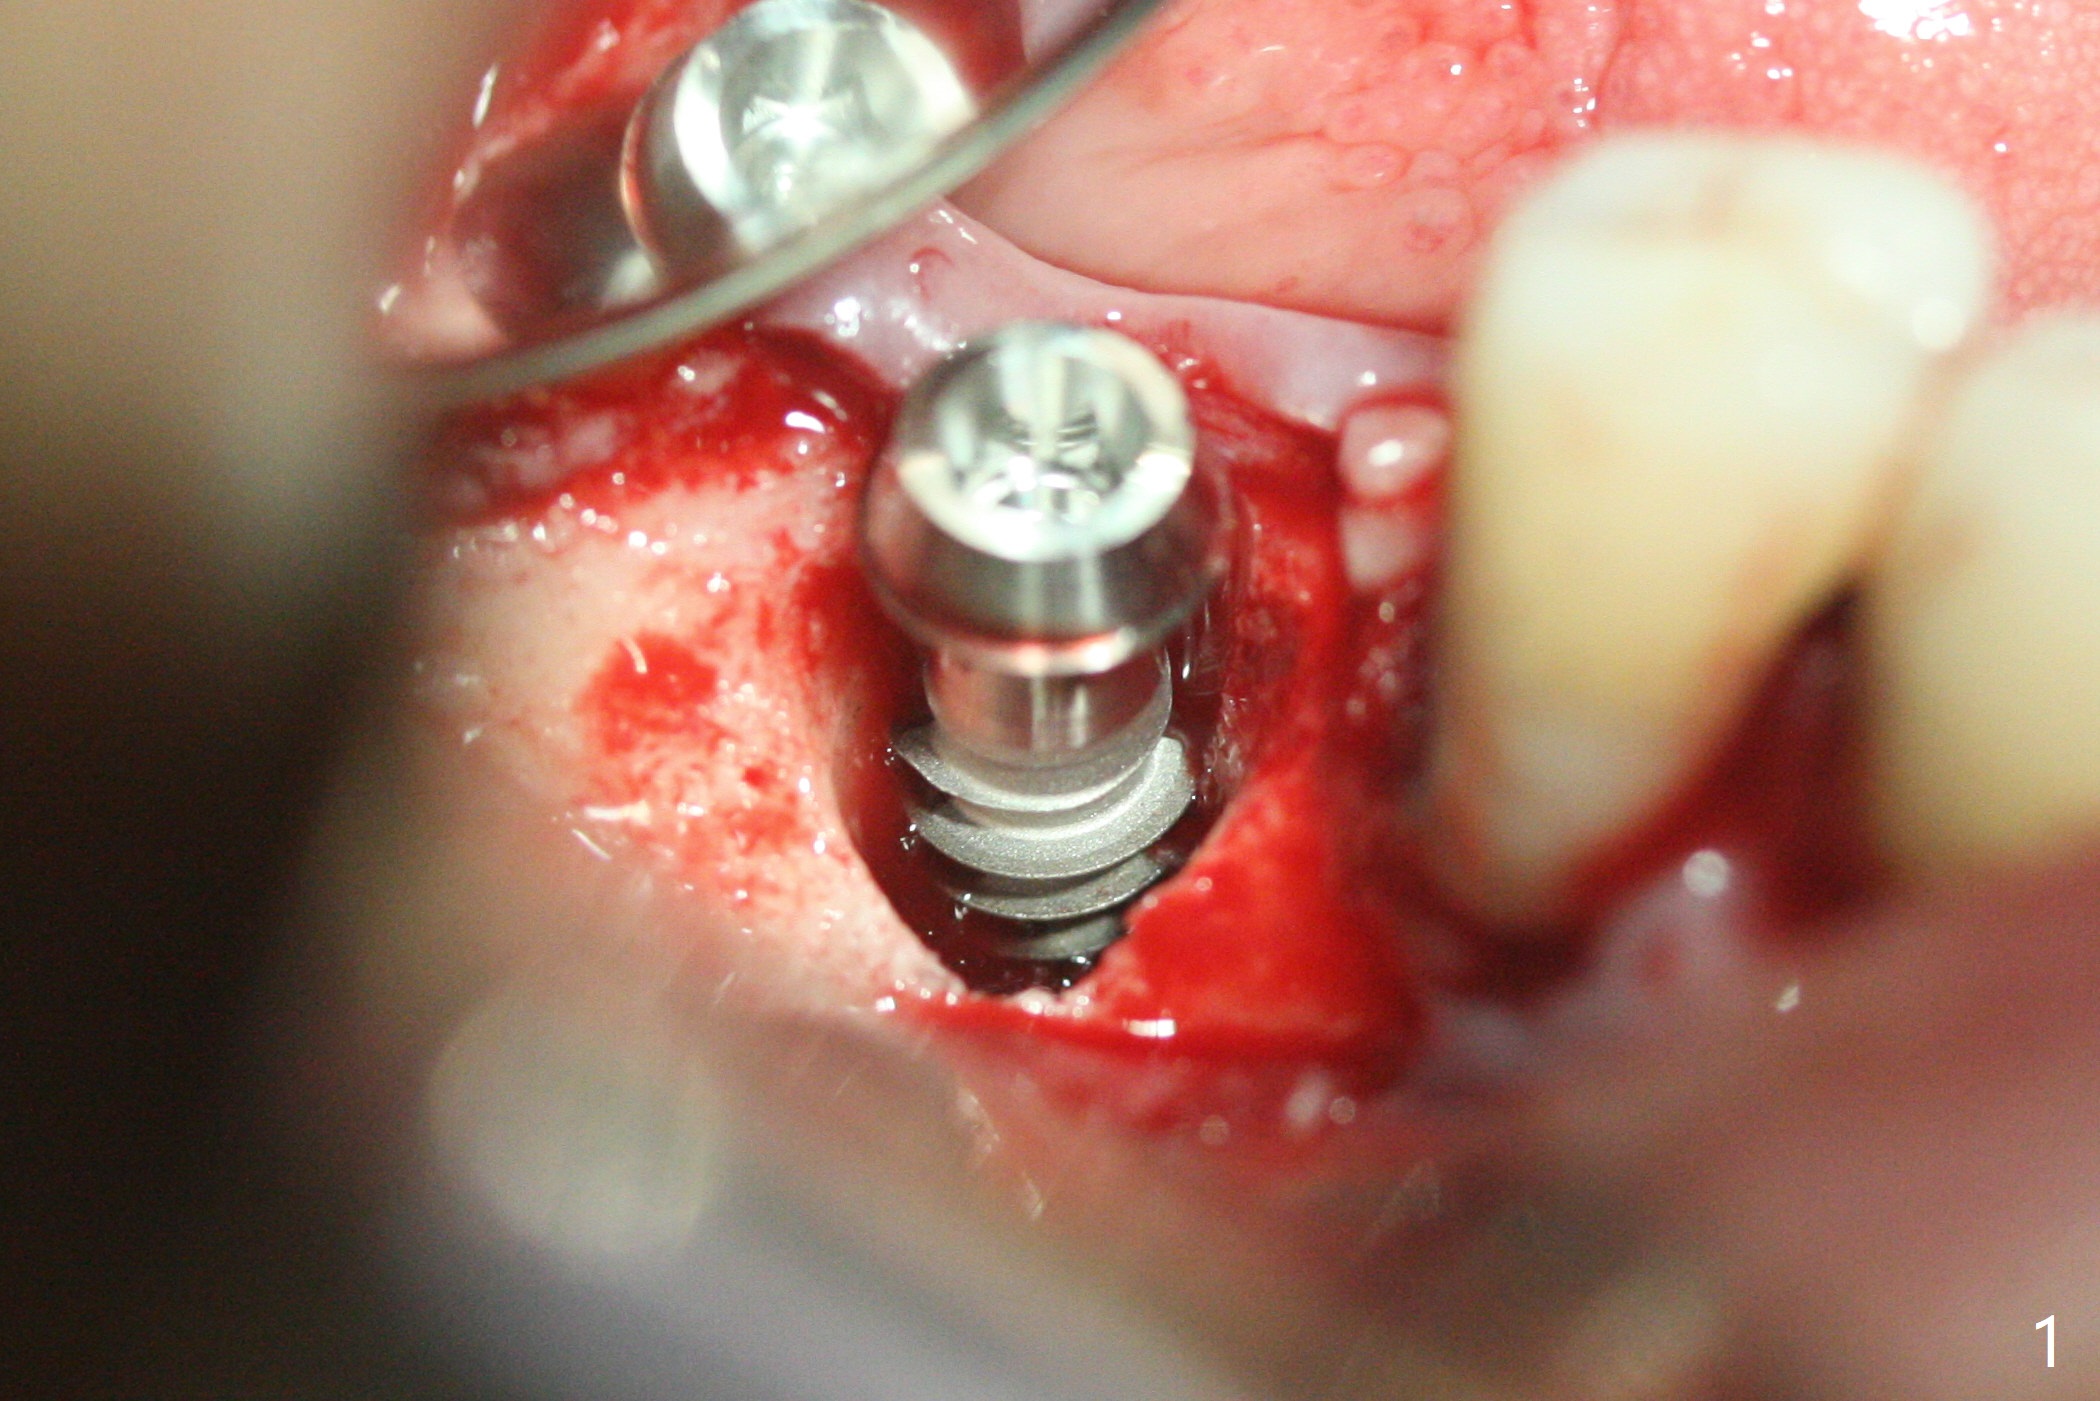

A 5x12 mm SM implant with periimplantitis at #30 is removed with a 5/6 mm trephine bur, small elevator and implant driver. A 3.8 mm Magic drill is used to start a new osteotomy in the lingual wall of the old one free hand. With the final drill (4.8x13 mm), a 5x11(3) mm Magicore is placed (Fig.1-4). The large buccal gap (Fig.2 arrowheads) is filled with allograft (Fig.3 *). The latter is covered by PRF, followed by suture. Periodontal dressing is applied around the 4.2x3 mm solid abutment and the coronal portion of the Magicore (Fig.4 <). The green outline in Fig.5 (CT coronal section) represents a new 5x10 mm implant (design), while the thick red line is approximately the long axis of the new implant. The implant heals in spite of buccal recession. Impression is taken with placement of a 4.3x5 mm solid abutment 4.5 months postop (Fig.6). Take follow-up CT to determine buccal bone formation.